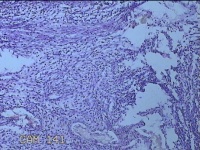

左卵巢囊肿

性别

女

年龄

32岁

临床诊断

左卵巢巧克力囊肿破裂

一般病史

下腹疼痛2天,加重10小时。

标本名称

大体所见

灰白暗红色囊壁样组织5.3x2x1.3cm一堆,表面糜烂,因已切开,囊内容物已流失,囊壁厚0.1cm。

图4